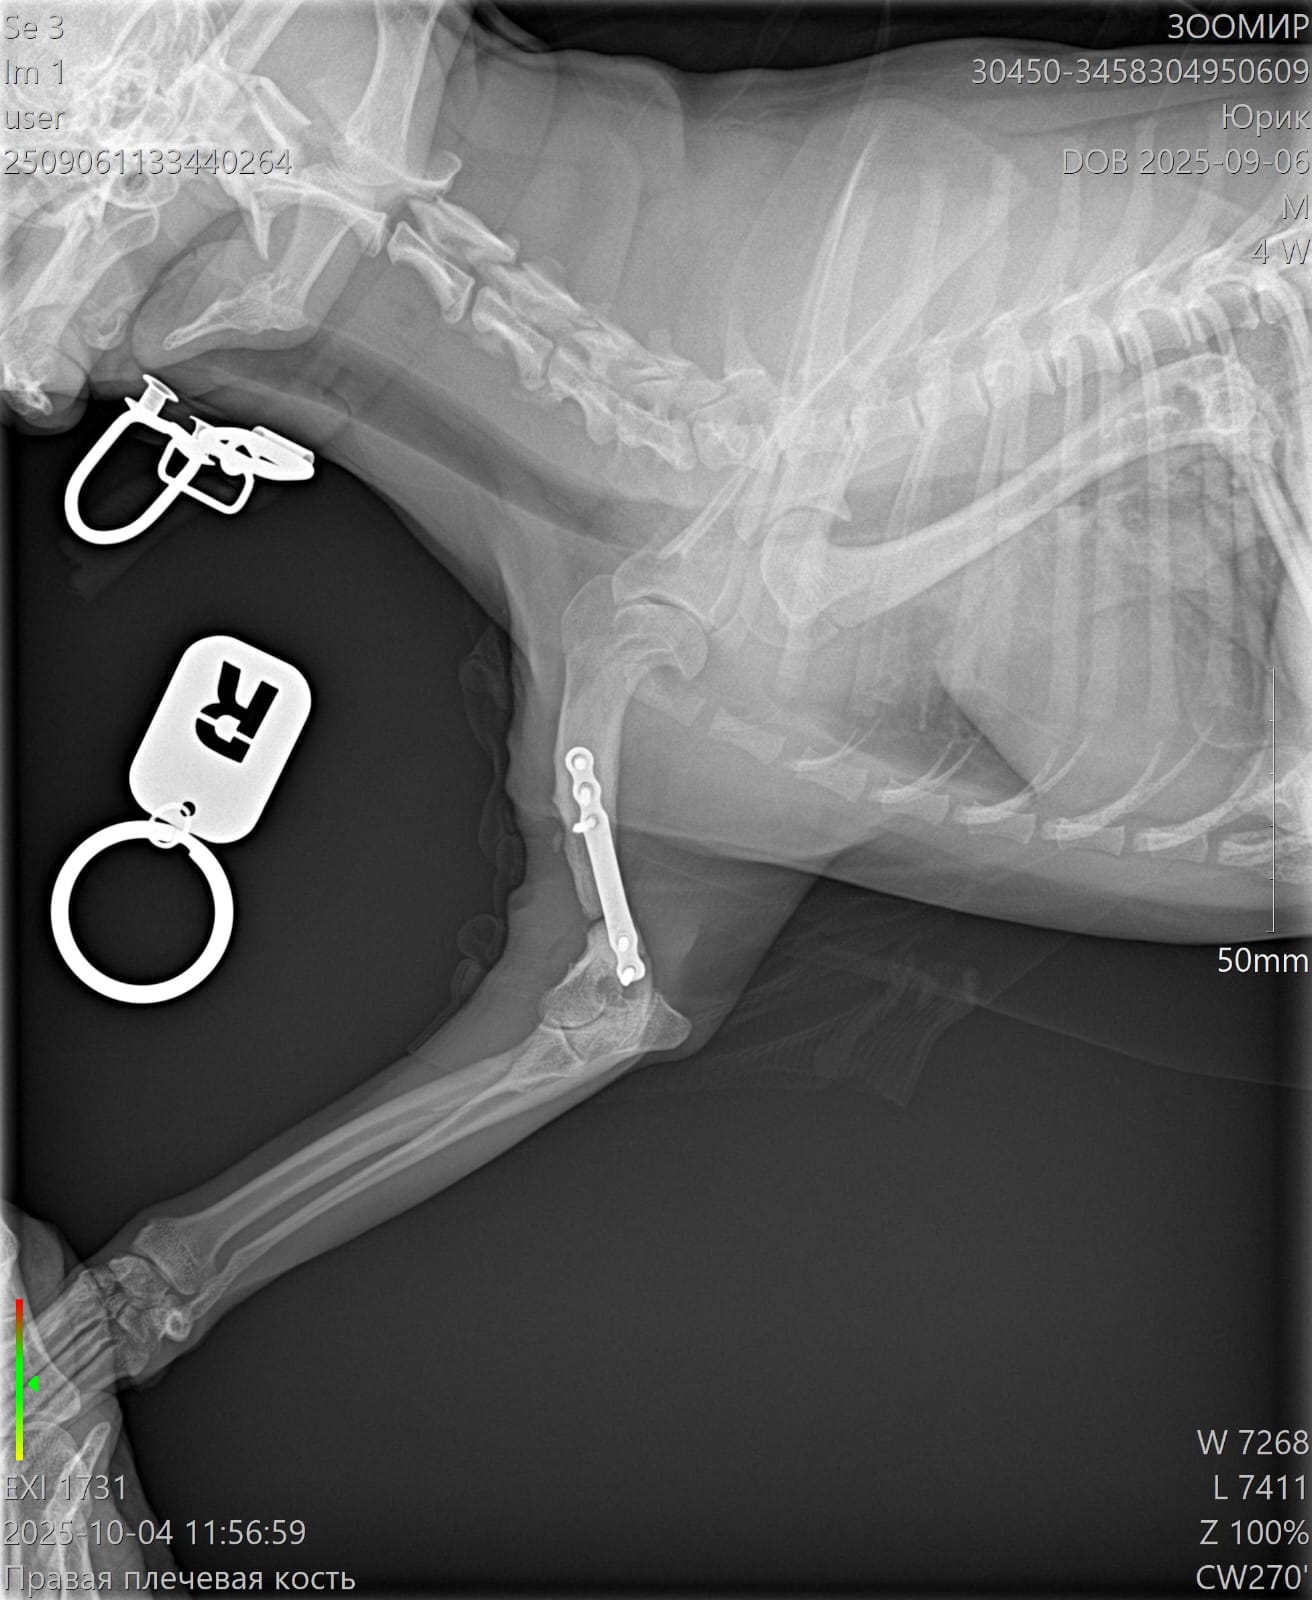

Сделали контрольный рентген - пока мозоли не видно:((((

Лапой на ровном немного пользуется. Но это за счет пластины.

Рентген

Юрик съездил сегодня на контрольный рентген.

Мозоль ОБРАЗОВАЛАСЬ. По центру она еще не очень плотная, но кость срослась.

Как Ольга паразита не оберегала, но на рентгене оказалась чуть погнутая пластина и один сломанный винт.

Снимать ничего не будем из конструкции, если не начнет отторгаться или двигаться.

Юрик. Взгляд изнутри